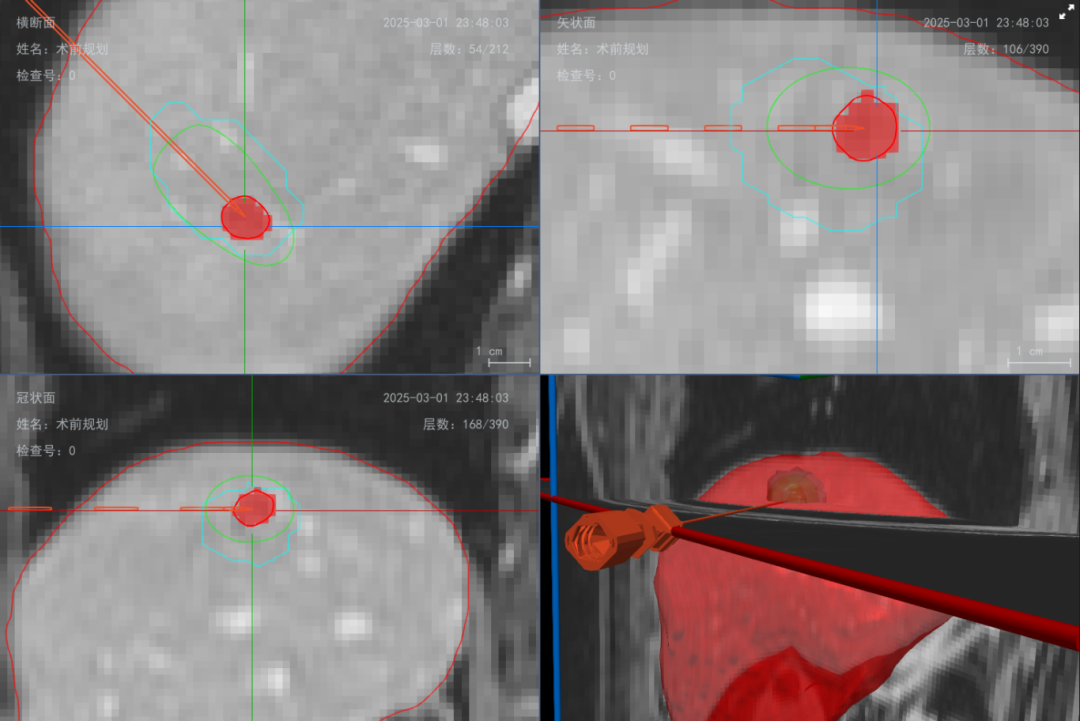

为解决这一临床痛点,德文医学推出了监测消融评估系统,可利用CT/MRI图像,通过快速图像处理,获得组织及病灶的多维度多视角图像、安全的进针方案及需要的消融范围。

在术前,系统基于患者CT/MRI影像数据,系统软件可实现高精度三维重建,真实还原病灶及其周边解剖结构,结合系统提供的距离测量、容积计算及模拟消融范围等功能,为规划个性化、精准化的消融路径与能量布控提供可靠依据。

在术中,通过实时动态显示微波能量场的分布范围,并将其与肿瘤的立体模型精确叠加,为病灶定位提供可视化、精准化参考支撑。

至此,德文医学监测消融评估系统通过“术前AI规划穿刺路径—术中双频能量精准调控与实时可视导航—术后即时影像评估”,构建了覆盖肿瘤治疗全流程的精准闭环。